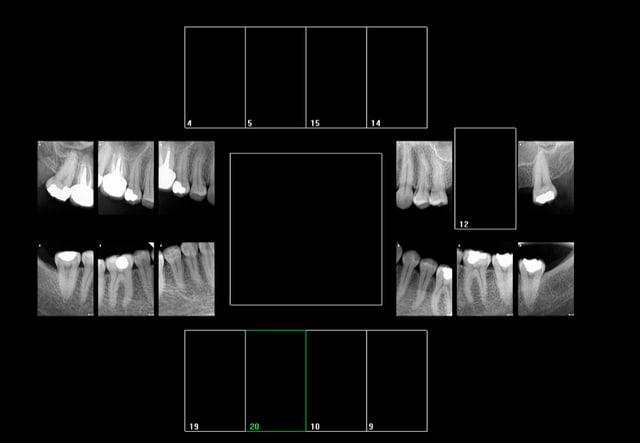

Signes d'appels : Douleur diffuse d'intensité moyenne + atcd de soins intensifs

HBQK 142 ( 8 radios)

17,14 24 27 37 35 44 47

Diagnostic :

Origine vraisemblablement 16 ( percussion légère) mais 17 possible aussi ( percussion légère + Froid).

Indication pour un cone beam vu que la rétro alvéolaire ne montre pas de lésion apicale.

Orientation thérapeutique : RTE 16 pour commencer ( tt endo insufisant)